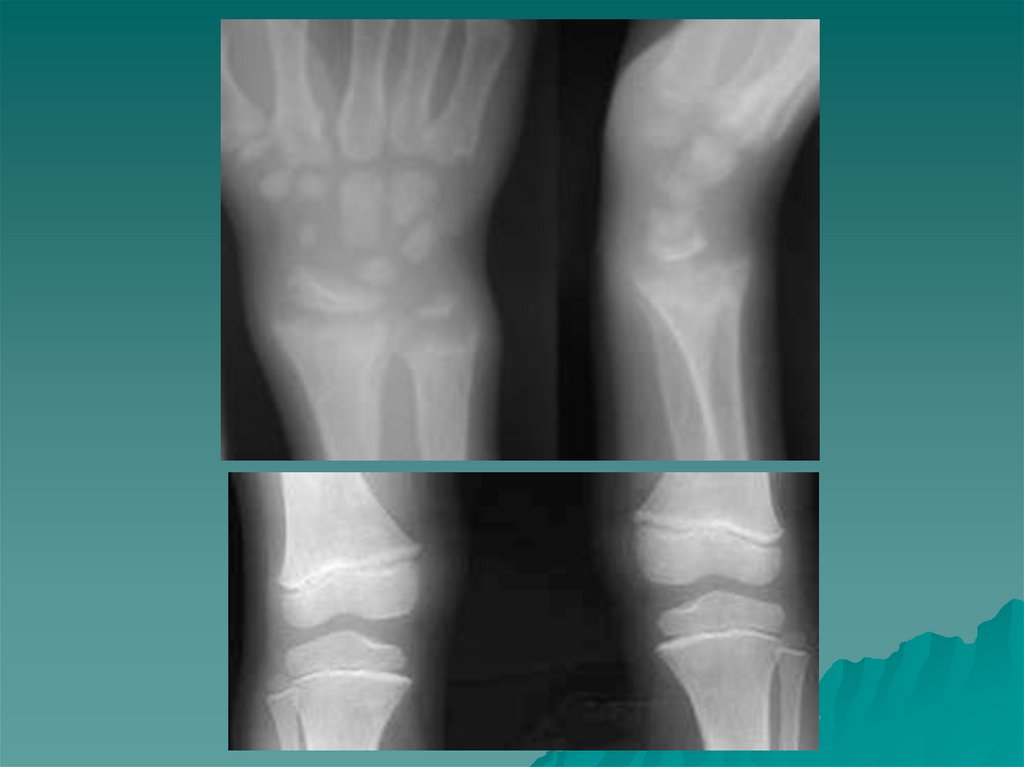

Рахит

Рахит у детей